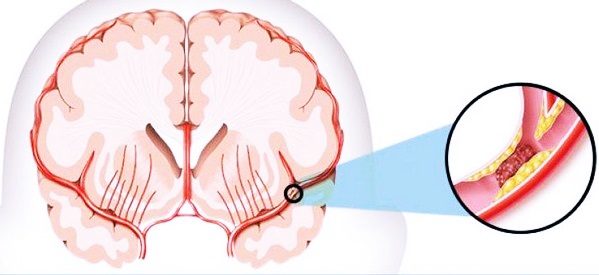

- Возникновение инсульта связано с закупоркой, сужением сосудов. Тогда развивается ишемическая разновидность недуга.

Из-за чего происходит инсульт ишемический? Общие причины ишемического инсульта – атеросклероз и гипертензия. Он может случиться в любом возрасте. Причины ишемического инсульта с гендерной предрасположенностью следующие:

- Ишемию. Нарушается кровоснабжение.

- Эмболию. Сосуд закупоривается эмболом.

- Атерому. Происходит патологическое дегенеративное изменение сосудистых стенок.

Эмболия связана с тем, что в сосуде собирается жировой сгусток. Его называют эмболом. Когда такой эмбол оказывается в сосуде, он закупоривает его. Кровоток перекрывается. Часто эмболия случается после операций на сердце. Также ее может вызвать аритмия.